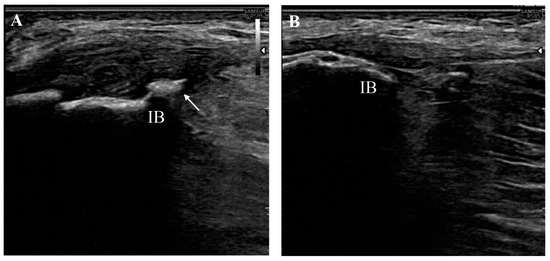

- Manske, R.C.; Wolfe, C.; Page, P.; Voight, M.L.; Bardowski, E. The Utilization of Diagnostic Musculoskeletal Ultrasound in the Evaluation of Gluteus Medius Tendon Pathology: A Perspective for Rehabilitation Providers. Int. J. Sports Phys. Ther. 2024, 19, 642–645. [Google Scholar] [CrossRef] [PubMed]